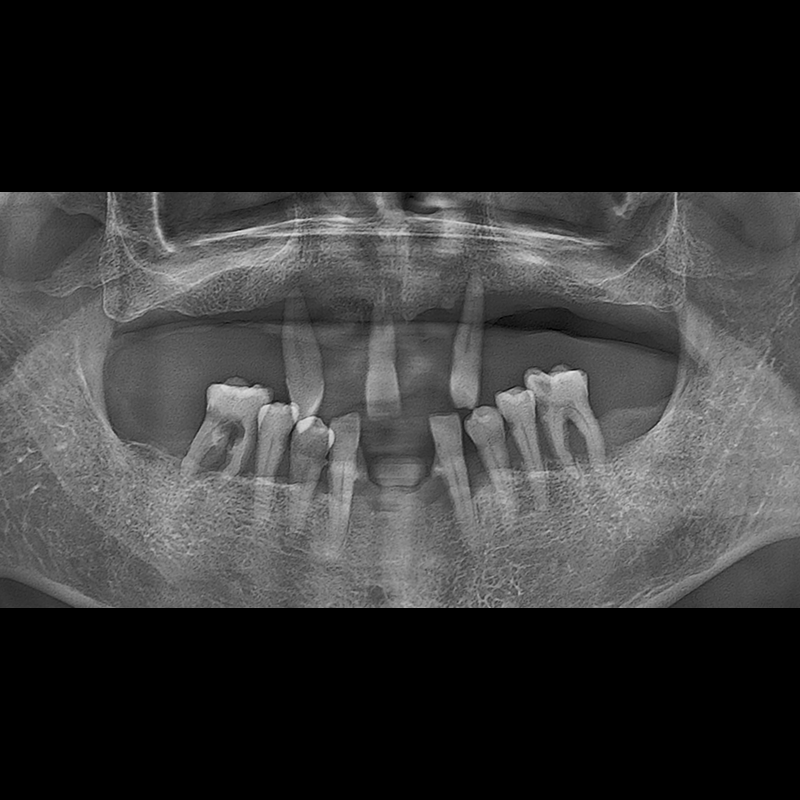

IMPLANT

BEFORE AFTER